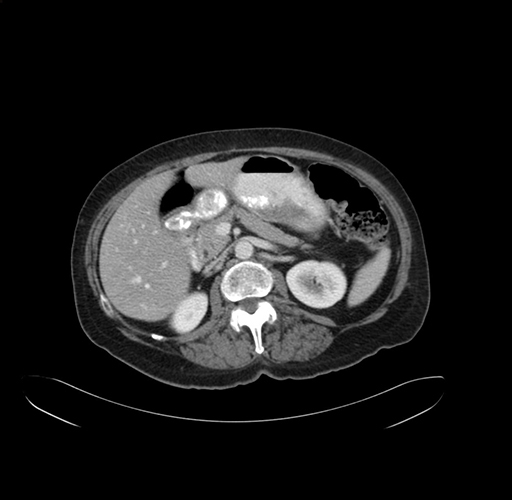

Axial Venous